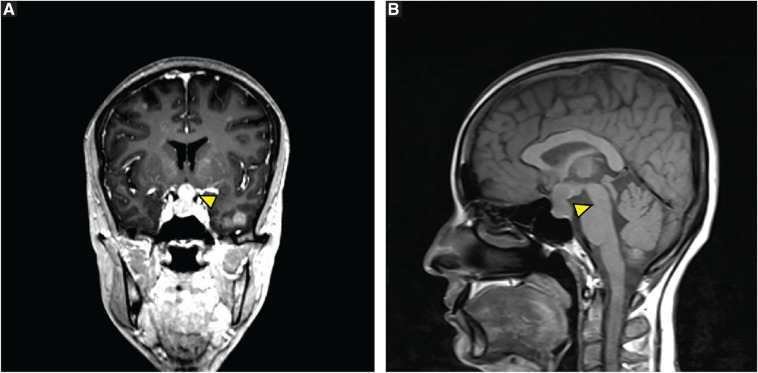

Case presentation: A 30-year-old female presented with respiratory symptoms and systemic complaints, initially suggestive of miliary TB. Further investigations revealed metastatic lung adenocarcinoma with pituitary metastasis, causing diabetes insipidus, hyperprolactinemia, adrenal insufficiency, and hypothyroidism. Treatment with targeted therapy involving osimertinib resulted in clinical improvement.